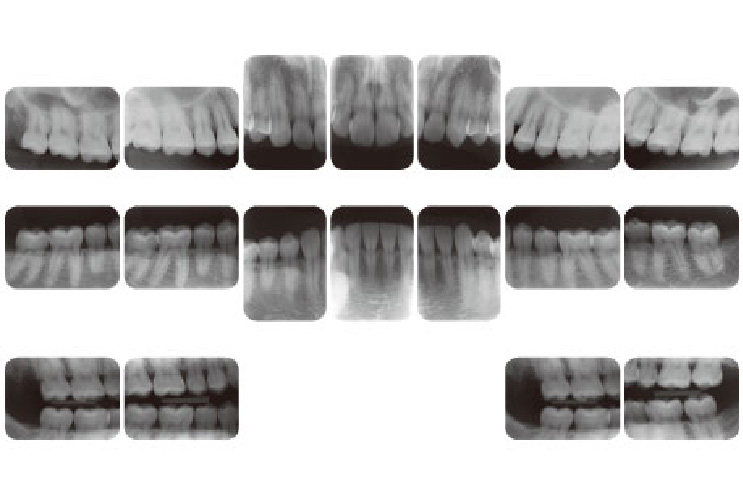

• ■レントゲン

レントゲンも規格性を重視し、1本1本の歯の状態を確認し、診断を行うために定期的に撮影を行います。の技量を超える分野も日本トップレベルの専門医に紹介することによってよりハイレベルな治療を受けることができます。

レントゲン

お口の写真やレントゲン写真、むし歯や歯周病の検査結果などをインターネット上で閲覧できるサービスを提供しております。患者様はいつでも手元のスマートフォンのアプリでご自身の状態を確認できます。